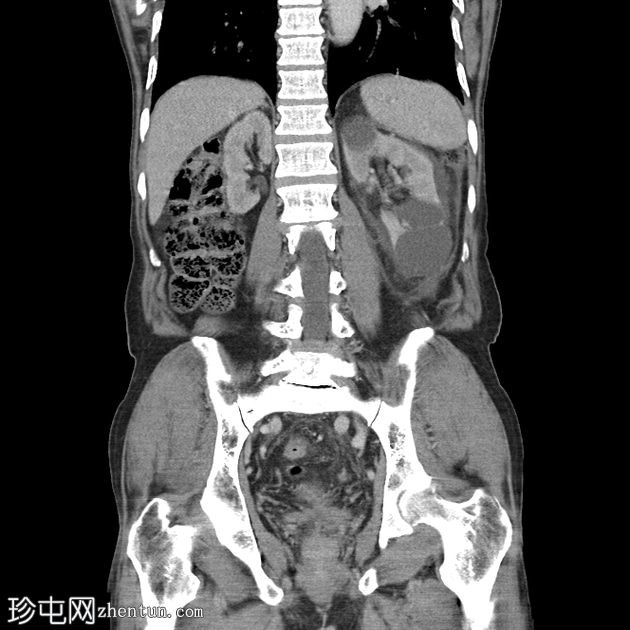

冠状位增强扫描(门静脉期)

门静脉期(冠状位、矢状位)可见左侧肾周间隙少量积液,液体沿左侧髂腰肌向下走行。延迟期可见造影剂外渗至左侧肾周间隙,提示尿囊肿。

左侧近端输尿管结石导致中度肾积水,结石大小为0.8 x 0.6 cm,左肾可见一微小非梗阻性结石。

左肾多发性单纯性囊肿。最大的肿块尺寸为 4.4 x 3.8 厘米。

影像学上,尿瘤通常表现为肾周或腹膜后间隙的液体积聚。在本例中,延迟 CT 扫描清晰地显示造影剂从(肾盏/肾盂/输尿管)渗出并积聚在肾周间隙,证实了尿瘤的存在。